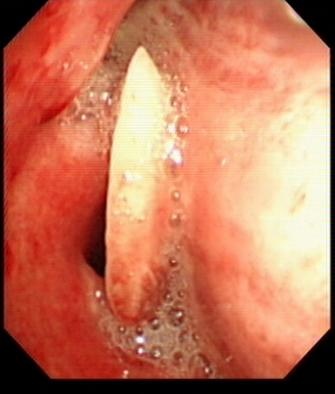

检查发现,老人的气道里面明显充血,气管镜下清楚地看到一块骨骼碎片卡在了右主支气管管口,最后被成功地钳夹出来了,原来是一个长约3cm两头极其尖锐的排骨碎片。

气管镜下的排骨碎片